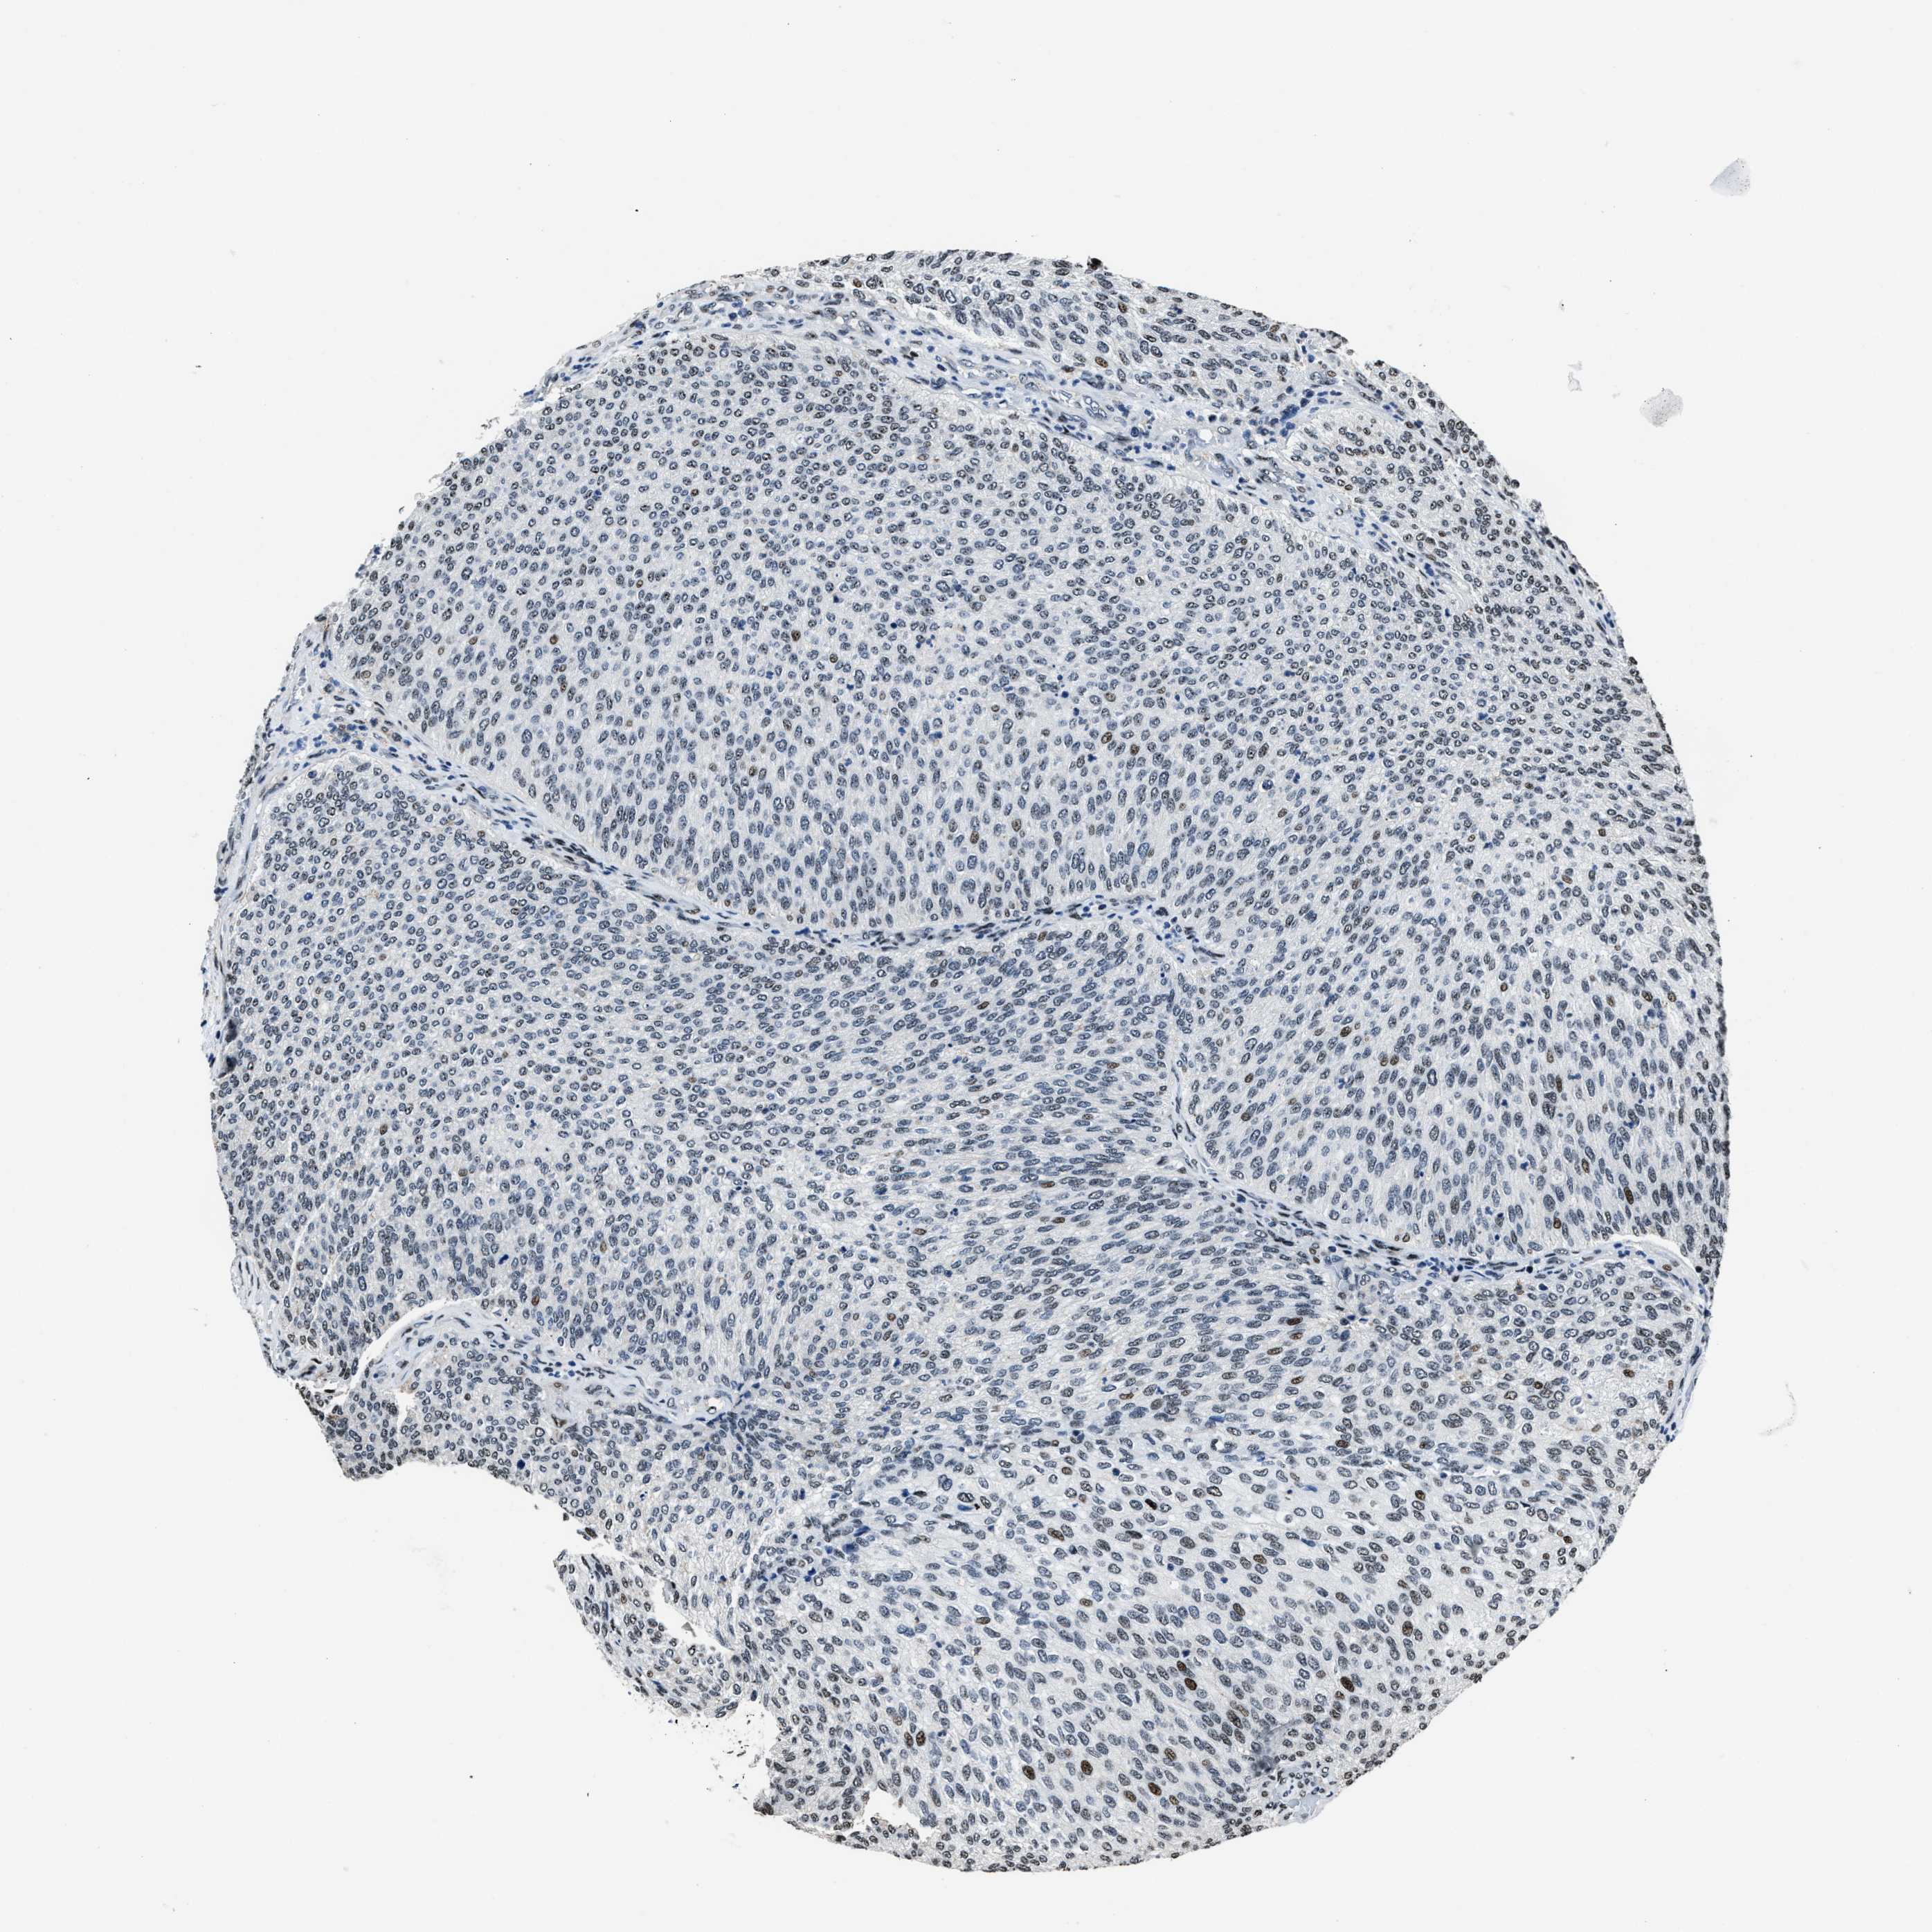

UROTHELIAL CANCER - Protein expressioni

A mouse-over function shows sample information and annotation data. Click on an image to view it in a full screen mode. Samples can be filtered based on level of antibody staining by selecting one or several of the following categories: high, medium, low and not detected. The assay and annotation is described here.

Note that samples used for immunohistochemistry by the Human Protein Atlas do not correspond to samples in the TCGA dataset.

Antibody stainingi

Antibody staining in the annotated cell types in the current human tissue is reported as not detected, low, medium, or high, based on conventional immunohistochemistry profiling in selected tissues. This score is based on the combination of the staining intensity and fraction of stained cells.

Each image is clickable and will lead to virtual microscopy that enables deeper exploration of all samples and also displays staining intensity scores, fraction scores and subcellular localization as well as patient and tissue information for each sample.

Antibody HPA020131

Staining

High

Medium

Low

Not detected

Intensity

Strong

Moderate

Weak

Negative

Quantity

>75%

75%-25%

<25%

None

Location

Urothelial carcinoma, Low grade

Urothelial carcinoma, High grade